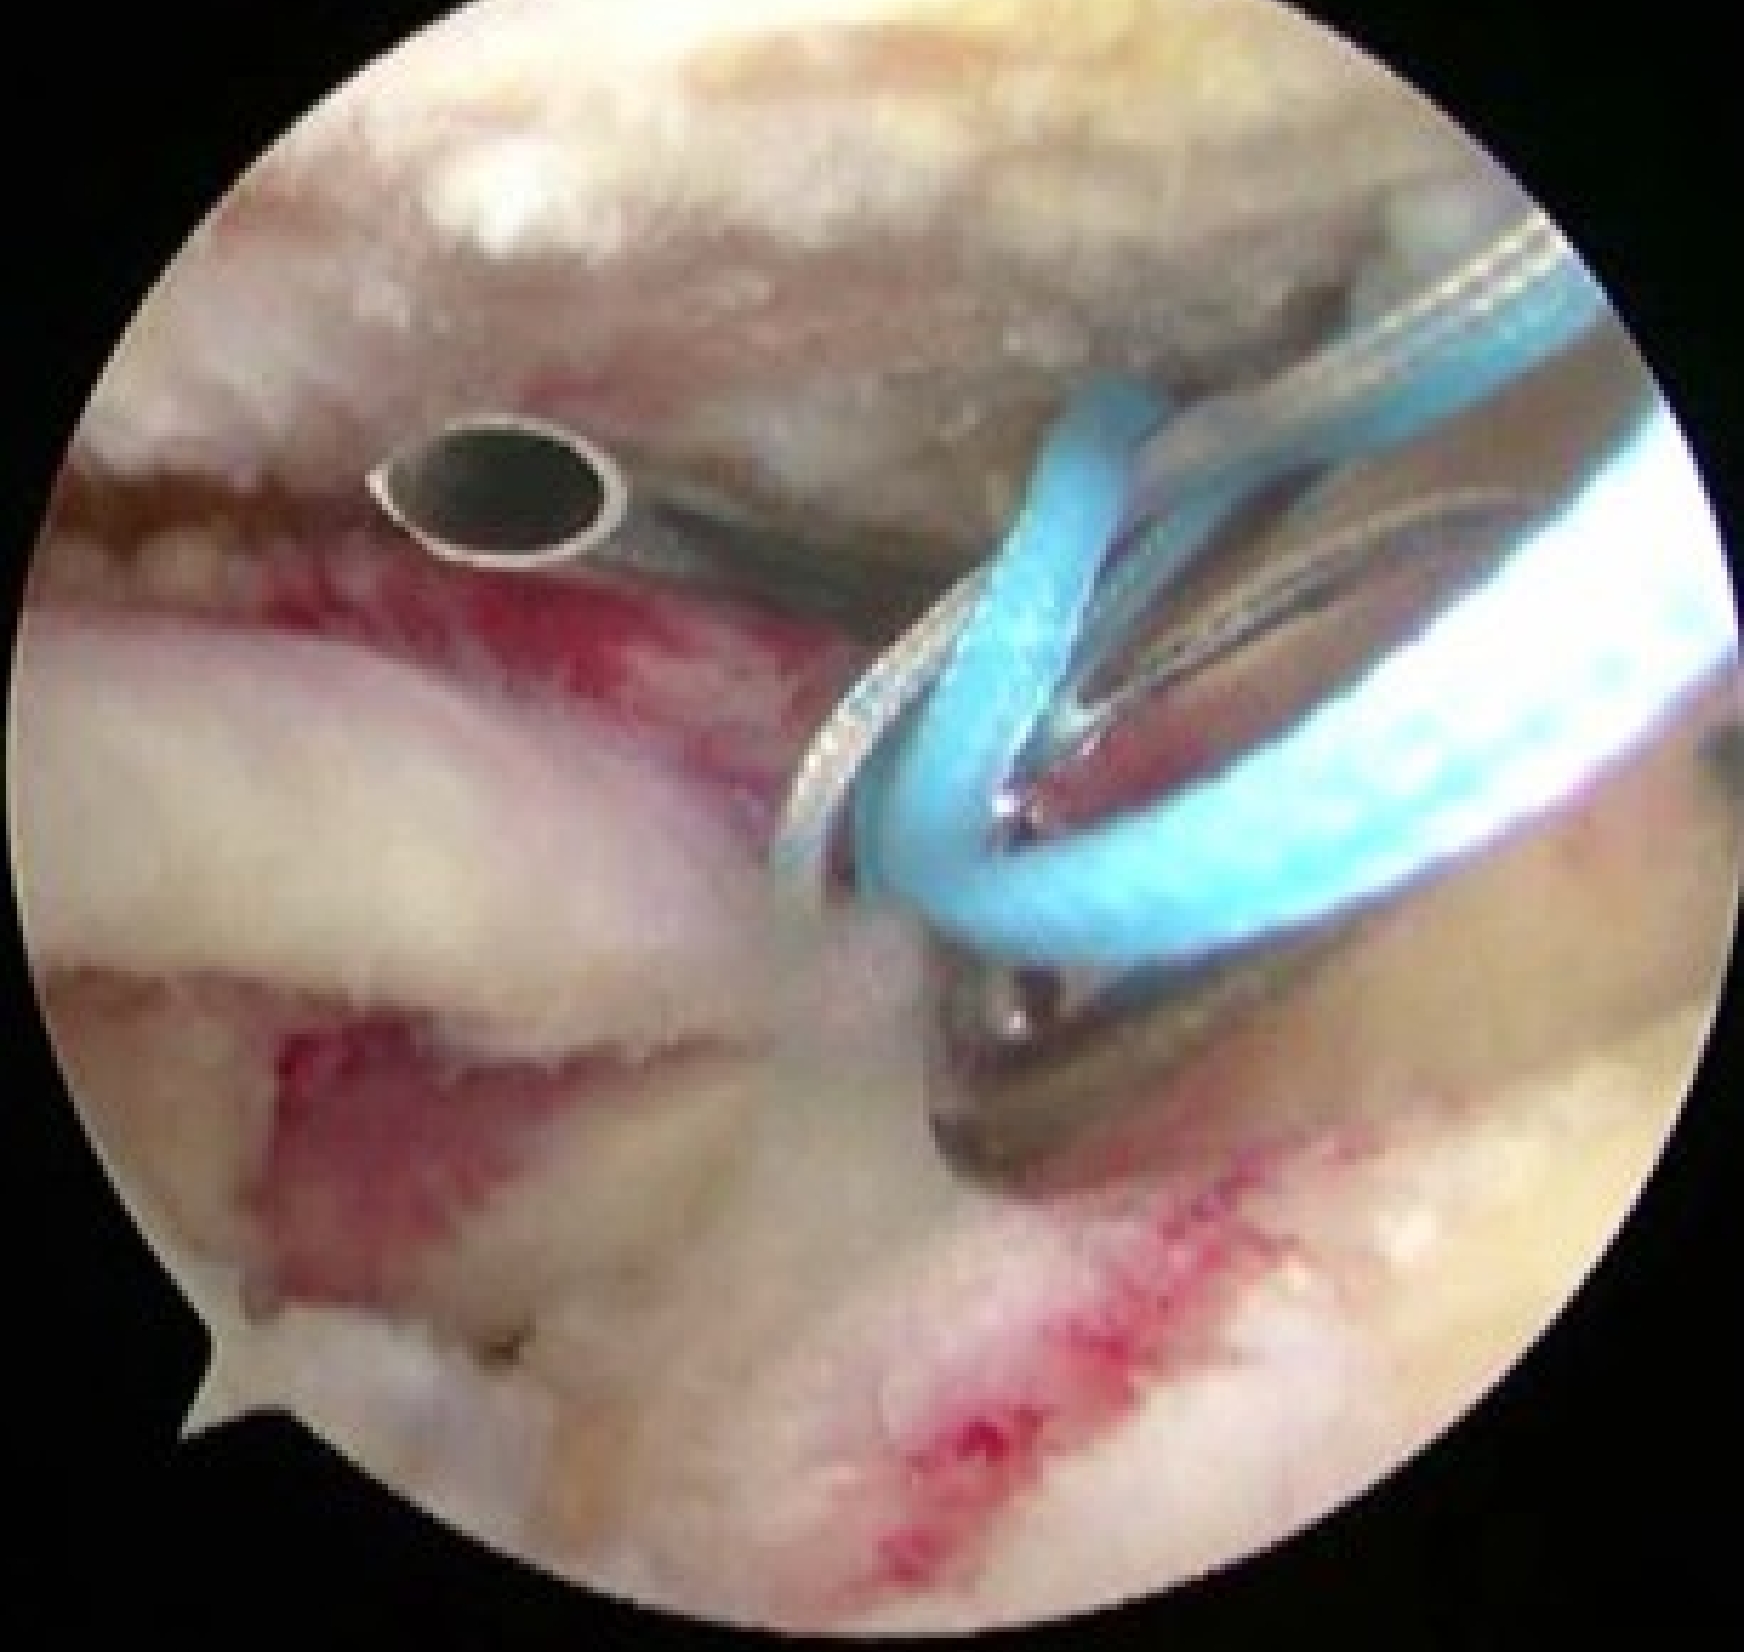

④関節唇修復

必要に応じて、上腕骨頭を肩甲骨関節窩に安定させる関節唇を修復します。